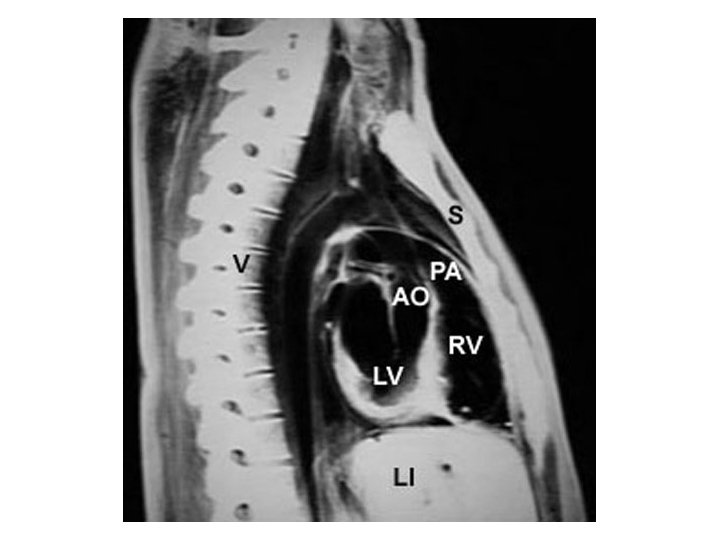

Left RV RA LV LA